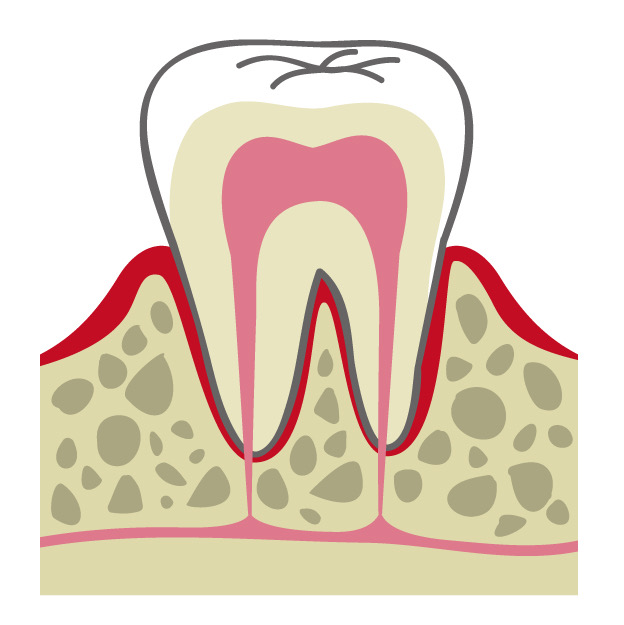

土台から整える治療

治療の結果を長く保つには、歯そのもの以上に「支える土台」の安定が重要です。歯周病で弱った歯ぐきや骨、歯の根の状態を検査結果から評価し、必要に応じて再生療法なども含めて選択肢を検討します。

目に見える部分だけを整えるのではなく、再発やぐらつきの原因となる要素に向き合い、支える組織まで丁寧に整える診療を心がけています。 -

02歯周病・

重度歯周病治療歯周病は痛みが少ないまま進行し、気づいた時には歯がグラつく、膿が出る、噛みにくいといった状態になりやすい病気です。けれど、重度でも「もう無理」と決めつける前に、歯ぐき・骨・噛み合わせの状態を丁寧に評価し、今できることを一つずつ積み上げれば、守れる歯はあります。

当院では検査に基づき、基本治療から必要に応じた外科的治療や再生療法の検討まで、長期維持を見据えて段階的に進めます。津市で歯周病を本気で治したい方に、寄り添える歯科医院でありたいと考えています。症例1